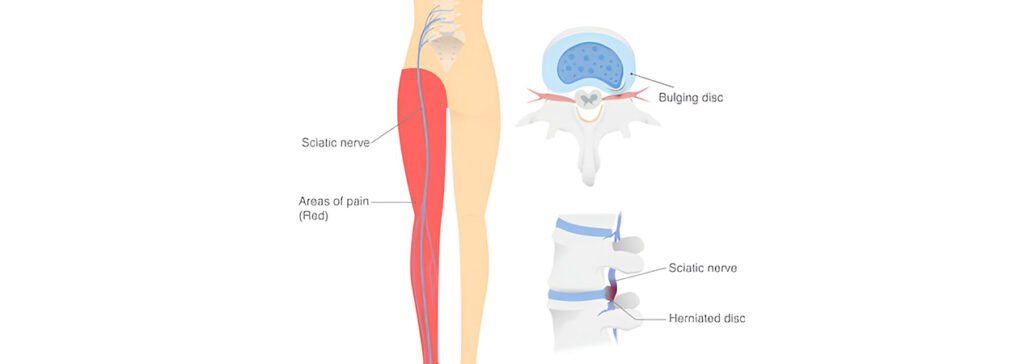

Stop the Shooting Pain: Managing Sciatica With Ayurvedic Therapies

Ayurvedic therapies effectively manage the shooting pain associated with sciatica by addressing its underlying causes. Herbal formulations like Ashwagandha and Turmeric provide anti-inflammatory benefits. Warm oil massages with Mahanarayan oil help stimulate circulation and alleviate tension. Additionally, lifestyle changes, such as incorporating anti-inflammatory foods and regular physical activity, support recovery and overall well-being. This holistic […]